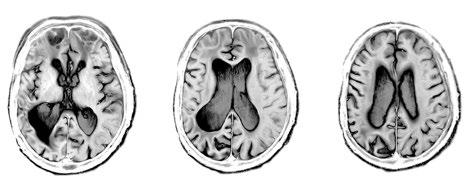

L’un des avantages les plus remarquables de l’imagerie cérébrale est qu’elle permet aux scientifiques d’étudier des cerveaux de personnes en bonne santé. Au début du XXe siècle, le seul outil pour voir à l’intérieur d’un cerveau était le scalpel. Les seuls sujets qui se prêtaient à l’étude étaient donc les patients atteints d’une maladie incurable ou suffisamment pénible pour qu’ils soient prêts à tout essayer. Sans oublier ceux qui avaient déjà dépassé la phase terminale. L’apparition

de l’imagerie cérébrale permettait désormais de comparer des cerveaux malades et des cerveaux sains.

L’imagerie par résonance magnétique, qui permet d’observer L’intérieur du cerveau humain